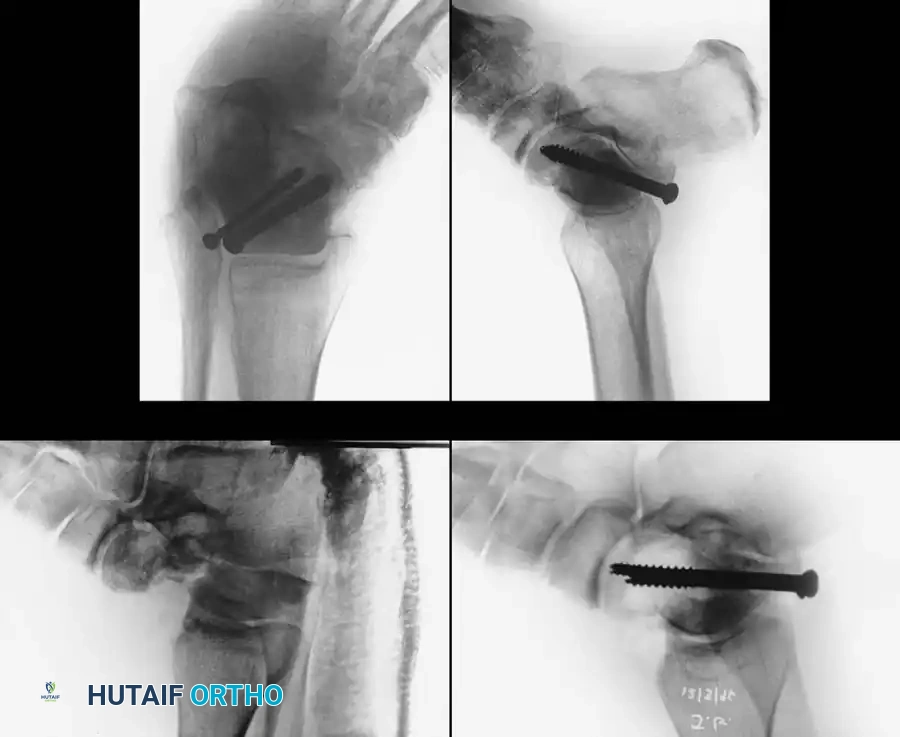

Reduction and Fixation:

Once anatomically reduced, provisional fixation is achieved with K-wires. Definitive fixation typically involves multiple lag screws (3.5 mm or 4.0 mm) placed from anterior to posterior, or posterior to anterior.

Fixation X-ray 1

Fixation X-ray 2

Posterior-to-anterior screw placement (via a posterolateral approach) is biomechanically superior as it engages the denser bone of the talar head, but it requires careful avoidance of the flexor hallucis longus (FHL) and the neurovascular bundle.

Post-op fixation 1

Post-op fixation 2

In cases of severe medial comminution, a mini-fragment plate (e.g., 2.0 mm or 2.4 mm) may be applied to the medial talar neck to act as a buttress and maintain length, preventing varus collapse.